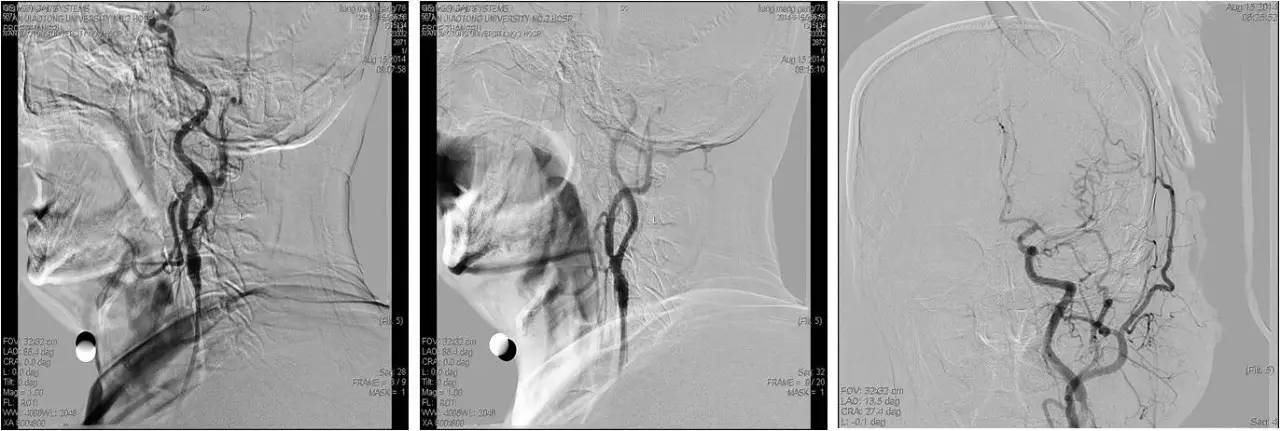

》急诊行DSA+动静脉联合溶栓+左侧颈内动脉狭窄球扩及支架成形术;

》乌拉地尔持续泵入,控制血压;

》rt-PA 5mg iv, 40mg ivd,维持1h;

》DSA:双侧颈内动脉起始部狭窄,狭窄率约80%,左侧大脑中前动脉显影差继而行超选择左侧颈内动脉动脉溶栓(rt-PA 5mg 推注),远端显影改善,行左侧颈内动脉狭窄球囊扩张及支架成形术。

术后

》术后常规给予补液治疗,多巴胺持续泵入,维持血压。

》术后8h,患者血压逐渐升高,多巴胺减量、停用,改用乌拉地尔泵入,收缩压多位于160mmHg左右。